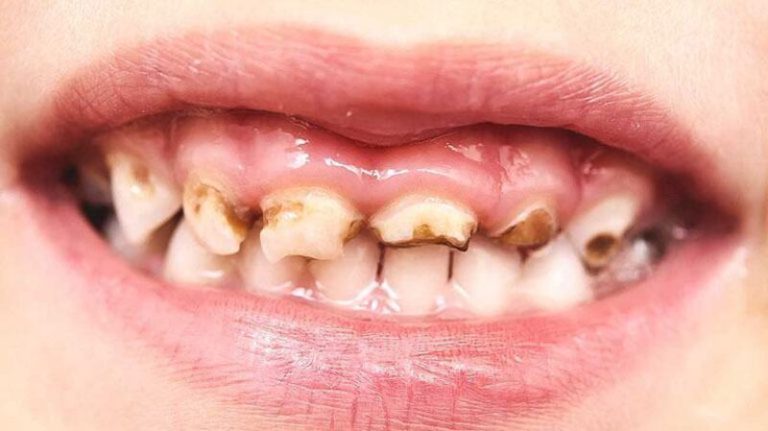

BỆNH ĂN MÒN CHÂN RĂNG, NGUYÊN NHÂN GÂY SÚN CỤT VÀ SÂU RĂNG Ở TRẺ NHỎ

Bệnh ăn mòn chân răng là tình trạng suy giảm men răng, mô dưới men răng và xương ở khu vực chân răng. Đây là một bệnh lý răng miệng thường gặp ở trẻ nhỏ,...